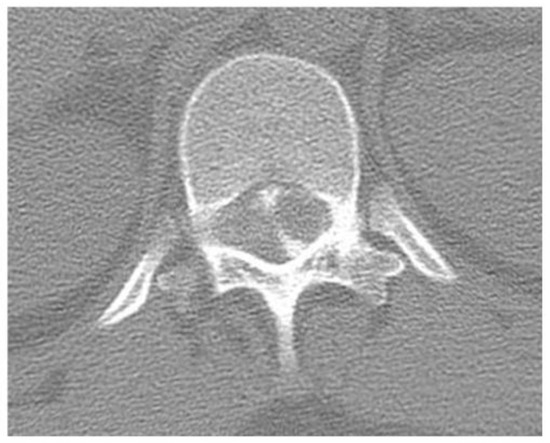

2.1. Case 1

2.2. Case 2